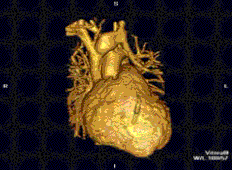

![]() نمونه ای از تصاویر CMRدر جهتهای مختلف تومور قلبی - در این مورد، میگزوم قلبی.[1] | |